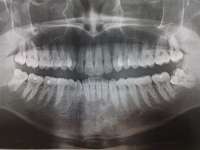

14732511028450.jpg (440Кб, 1866x1140)

14732511028541.jpg (378Кб, 2068x1160)

14732511028612.jpg (939Кб, 3060x1640)

ОПТГ восьмимесячной давности. Сейчас всё, по идее, хуже уже. Но свежее снимка нету.

>>514011

Вчера делал панорамный снимок. Всё как >>513480 сказал, ортодонт взял его только посмотреть. Внимание, вопрос знатокам, ортодонт посмотрел на второй пикрелейтед и сказал, что зуб в котором штифт нужно переделывать - канал не полностью залечили, а так же второй зуб - там тоже проблема с каналом и что если ставить брекеты, то им обоим придет пизда. Когда это лечить не понятно, времени в обрез, завтра пойду к своему врачу который год-полтора назад мне эти зубы лечил, послушаю что скажет. В то, что она плохо сделала не хочется верить, но нужно быть реалистом.

Еще вопрос, сегодня пидорю зубы и вижу ДЫРУ, ЧЕРТОВУ ДЫРУ В ДЕСНЕ около места, из которого мне выпилили зуб мудрости. Еще вчера этой дырки не было, засунул туда ершик, дырка оказалась глубокая, вытащил оттуда петрушку, попутно отложив немало так кирпичей. Завтра побегу к хирургу. Всё это уже знатно так заебало, за лето потратил на брекеты, пломбы, снимки, лекарства и прочие операции больше 40к и конца этому не видно.